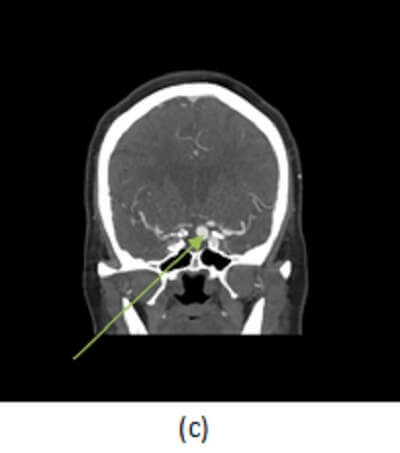

Figure 1: (a, red arrow) non contrast head CT demonstrates a rim calcified mass in the left cavernous sinus projecting towards the suprasellar space. (b, blue arrow) Axial image from a CT angiogram shows vascular enhancement of this mass . These findings are consistent with an aneurysm, likely fusiform. (c) Coronal minimum intensity projection from the CTA shows fusiform dilation of the left cavernous carotid.